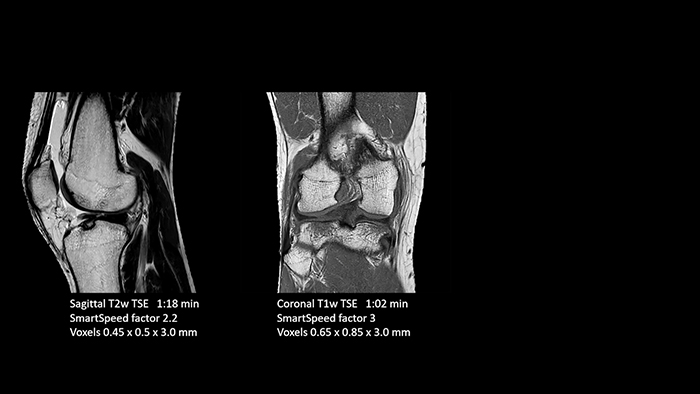

Previously, the practice wasn’t able to use 3D imaging on all joints, because the time required was too long, and on some joints it was simply not possible to achieve a good quality image, Dr. Schröter says. “Now, with SmartSpeed we consistently use 3D imaging for all joints and can thus discover the smallest changes, for example in the cartilage. And that, of course, helps us in making a detailed diagnosis.” Dr. Schröter says their MSK images show high contrast and extremely high quality. He mentions the menisci as an example. “We use a 3D proton density weighted fatsat sequence, thickness is 0.3 mm and scan time 3 minutes. The MPRs show an unbelievable resolution. Very small tears and even fraying of the tip of the meniscus become visible, which is normally only possible in arthroscopic surgery. When imaging the small joints of the fingers and the thumb we achieve extraordinary quality. Using SmartSpeed we succeed in displaying even very small structures anatomically correct, enabling us to see the extent of possible injuries. Tendons and ligaments appear with higher resolution so we can better see the injury pattern and describe and delimit it. Our referring physicians are fascinated by the extraordinary quality and high level of detail of the images. Patients are happy that the examination does not take too long. We hear from patients that it took a lot less time than they expected. This is especially important when scanning patients who are very uncomfortable in the MRI environment.”

SmartSpeed is used to reduce scan times. All three PDw orientations were obtained with only one 3D sequence using SmartSpeed. Performed with 1.5T Ambition X, 16ch dS Knee coil.

With these 3D scans we can create freely selectable MPRs that are pin-sharp, allowing us to easily see pathological changes.”